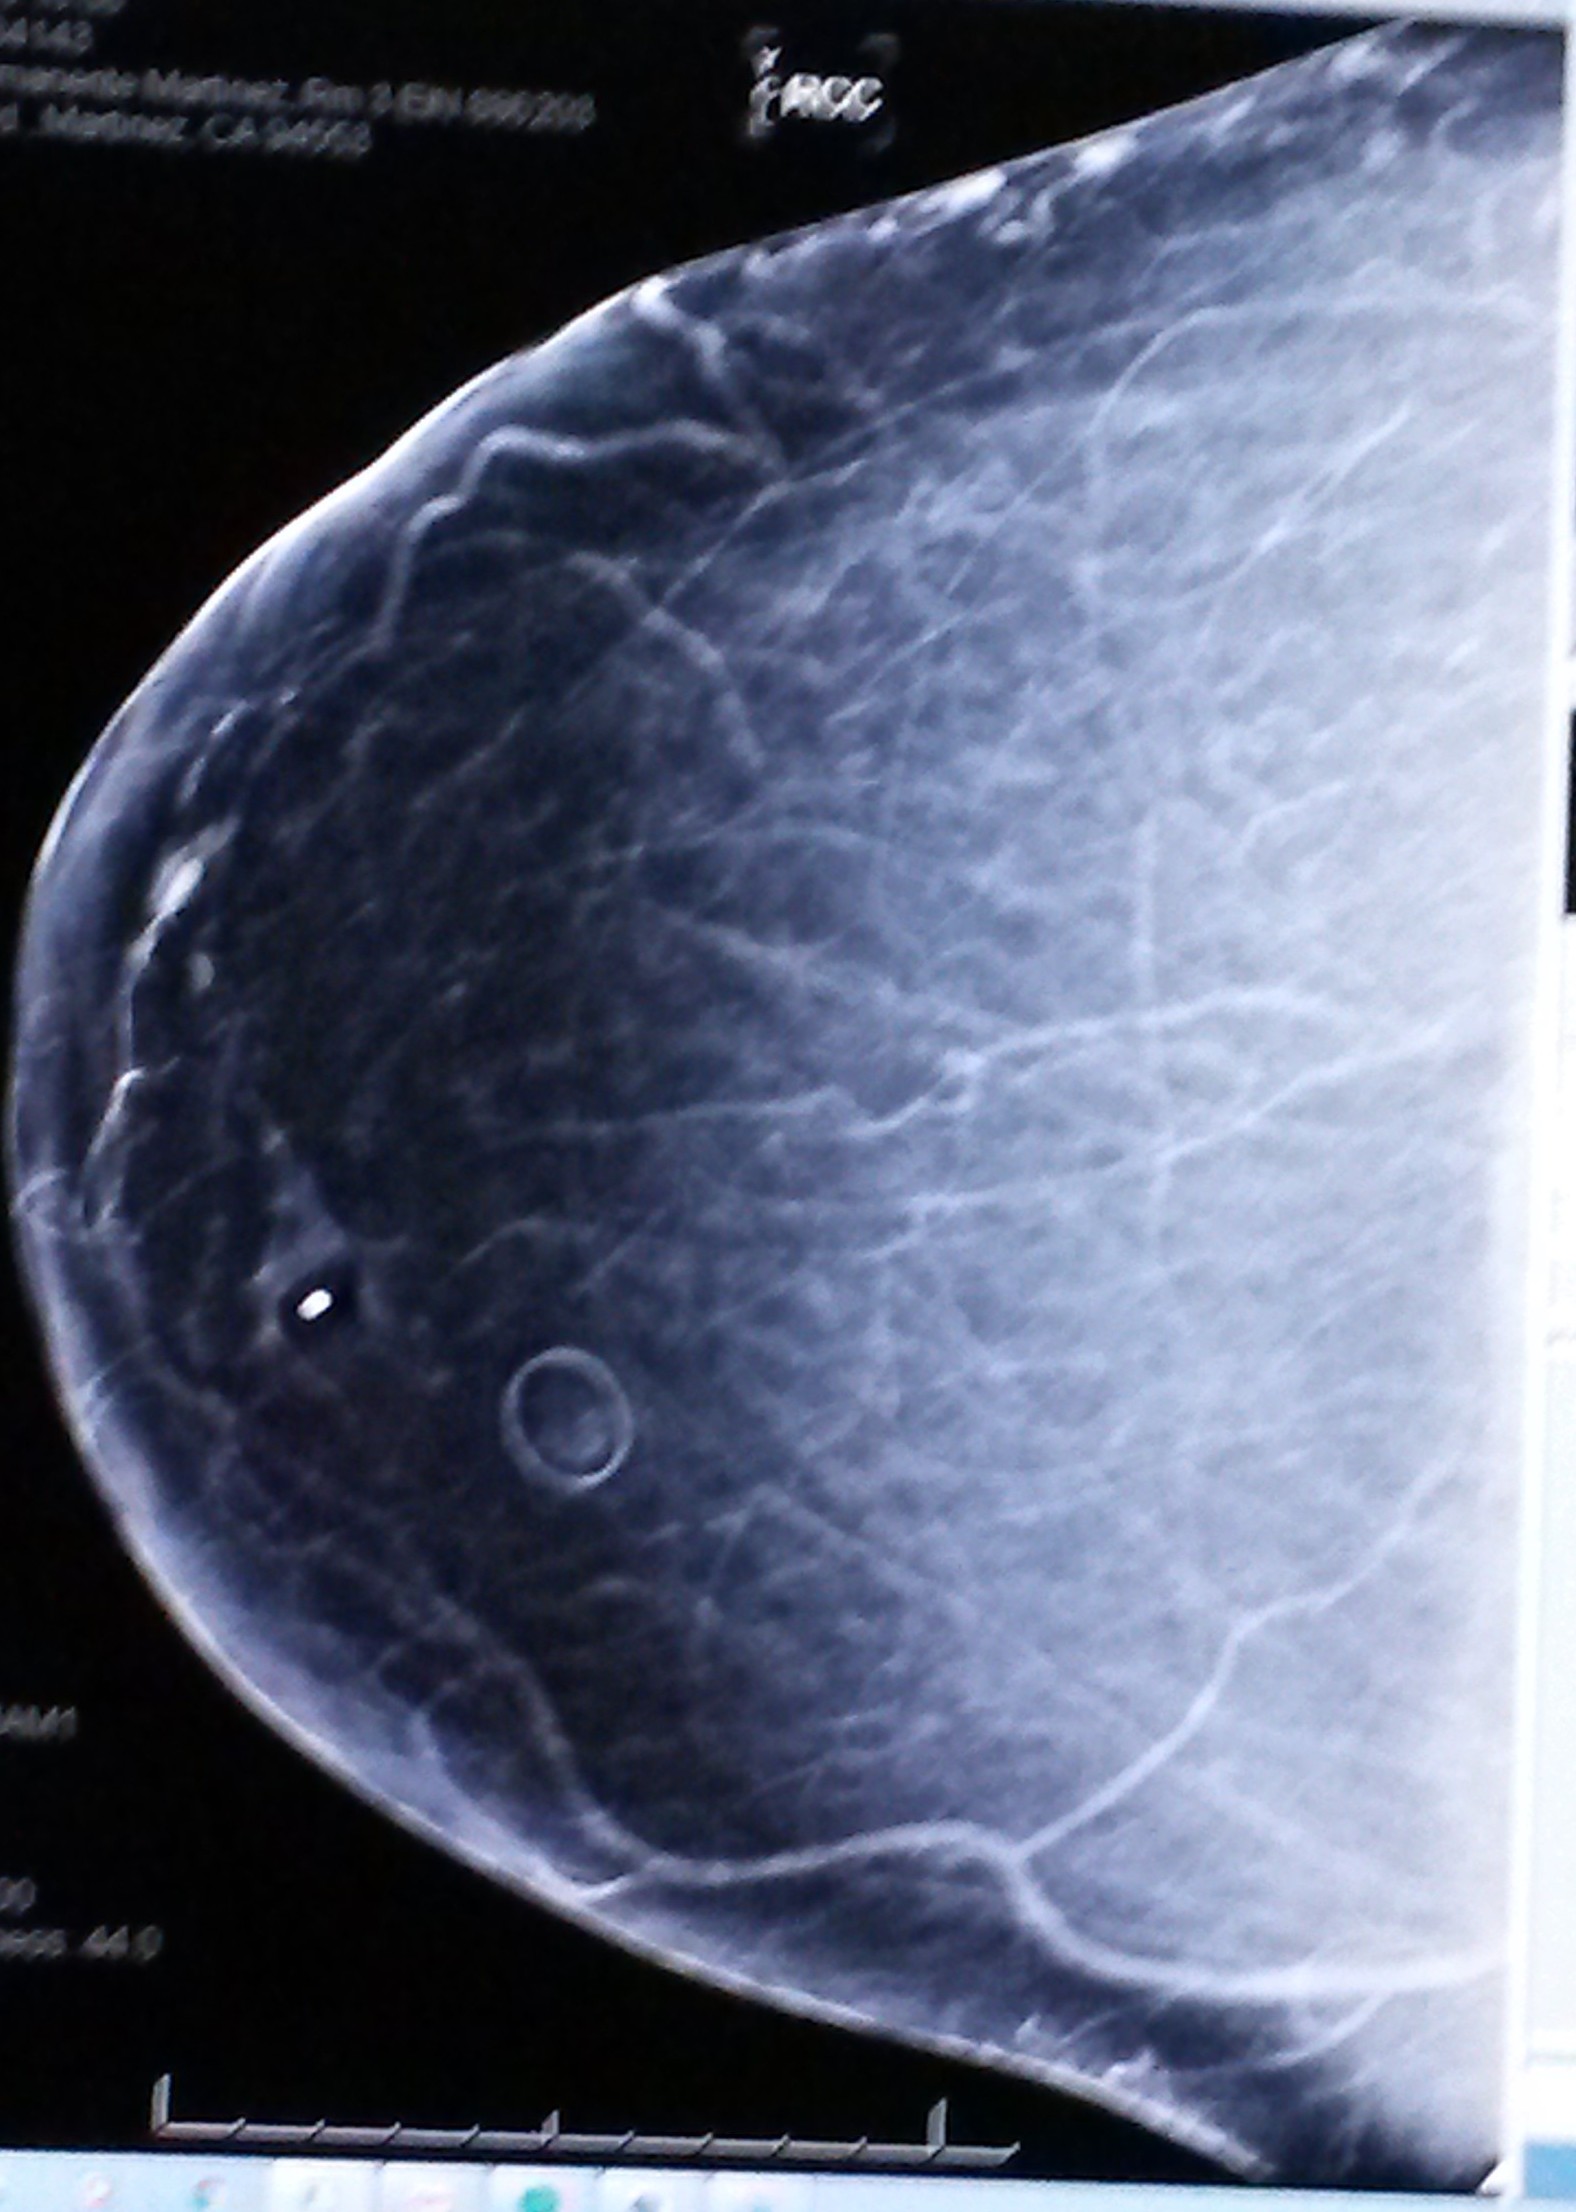

This was taken on 8-24-2016 - Mammogram noting the toward the curve...that's the Fibrelos Bump spoken of. Patient took photo of it with her phone.-->Photo to Right

This was taken on 8-21-16: day Patient saw the "Fibrelos Pressure Bruise". On August 21, 2016, this was what led her to the doctors office for a Mammogram.